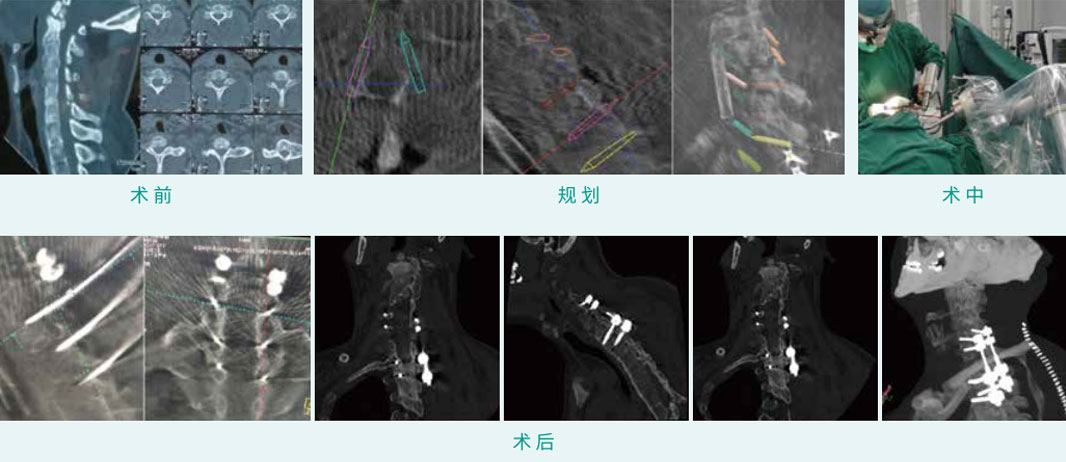

TiRobot ? C5,C6 Lateral Mass Screw Fixation and T1,T2 Pedical Screw Fixation

天玑? 辅助C5, C6侧块螺钉内牢靠术合并T1, T2椎弓根螺钉内牢靠术

基本情形:患者男,,,,,39岁,,,,,颈椎骨折(C2, C7),,,,,强直性脊柱炎

机械人累积用时:30分钟

植入物:4枚侧块螺钉,,,,,4枚椎弓根螺钉

病例泉源:北京积水潭医院 刘亚军